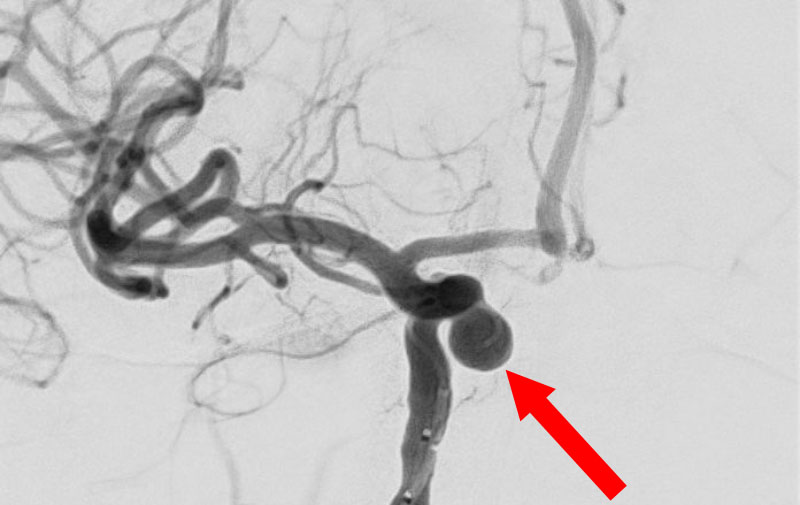

No.1592 手術前

No.1592 手術中

No.1592 手術後